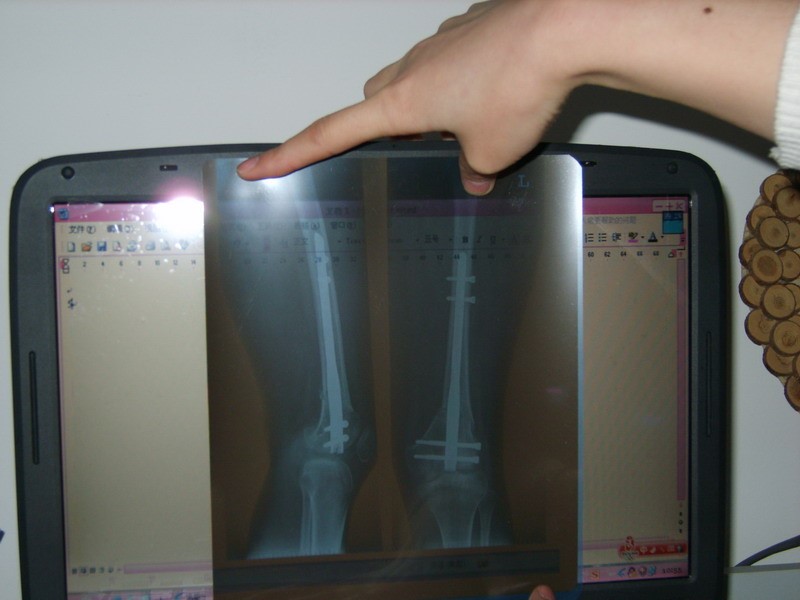

手术前诊断报告:北京医疗集团涿州医院

左膝外翻畸形,行走多疼痛,易摔倒,左腿细,建议手术矫形。王佐明

2008年4月7日    骨科

左膝因小时意外摔倒,导致外翻畸形7年,左膝走路伴疼痛,左腿比右腿细2公分,诊断为左膝外翻。建议住院进行手术治疗。高扬

12岁在水泥台阶上摔了左腿,导致外翻畸形,2008年4月11日在山东泰山医学院附属医院做了手术,三个月拆掉石膏后不能弯曲。开始是在医院采用医生强行扳曲和CPM机,以及草药熏洗相结合的治疗方法。第一次扳时,我痛得上了氧气,另一个病房的姐姐则是一个星期都不能下床,她的腿已经残废了。经过一个多月这样的锻炼,可以弯曲100°(内角),过程真的很痛苦,疼得整晚的睡不着觉,而且白天锻炼之后,经过一晚上,第二天还是回复僵直状态。由于太过痛苦,所以上网寻求治疗方法,偶然发现中国关节粘连网,打电话咨询后知道是南昌的一个诊所。刚开始心里是有点怀疑的,不过妈妈看我太痛苦,而且她一直坚信我会好起来,所以第二天(2008年8月24号)就独自去了那个诊所。

08年12月7日传图如下(已完全康复,患侧腿恢复到和健侧腿内交度数一样)